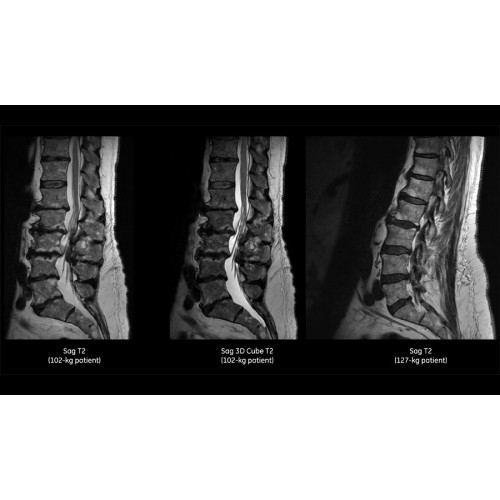

Детализация изображений

Система SIGNA Pioneer воплощает поразительные достижения в области визуализации. Передовая технология Total Digital Imaging (TDI) позволяет добиться большей четкости изображений и на четверть повысить соотношение сигнал/шум.

• Технология Digital Surround Technology (DST) — это новая технология объемной оцифровки данных, объединяющая сигналы от каждого элемента катушки. Прекрасное соотношение сигнал/шум и чувствительность поверхностных катушек в сочетании с превосходной однородностью и высокой проникающей способностью встроенной радиочастотной катушки — все это позволяет создавать качественные изображения не только позвоночника, но и всего тела.

Помимо технологии 97 РЧ-каналов, SIGNA Pioneer использует магнит 3.0Т высокой однородности, предназначенный для повышения качества визуализации во всех областях, а также закладывающий прочный фундамент для долгосрочных инвестиций и роста клинических возможностей.